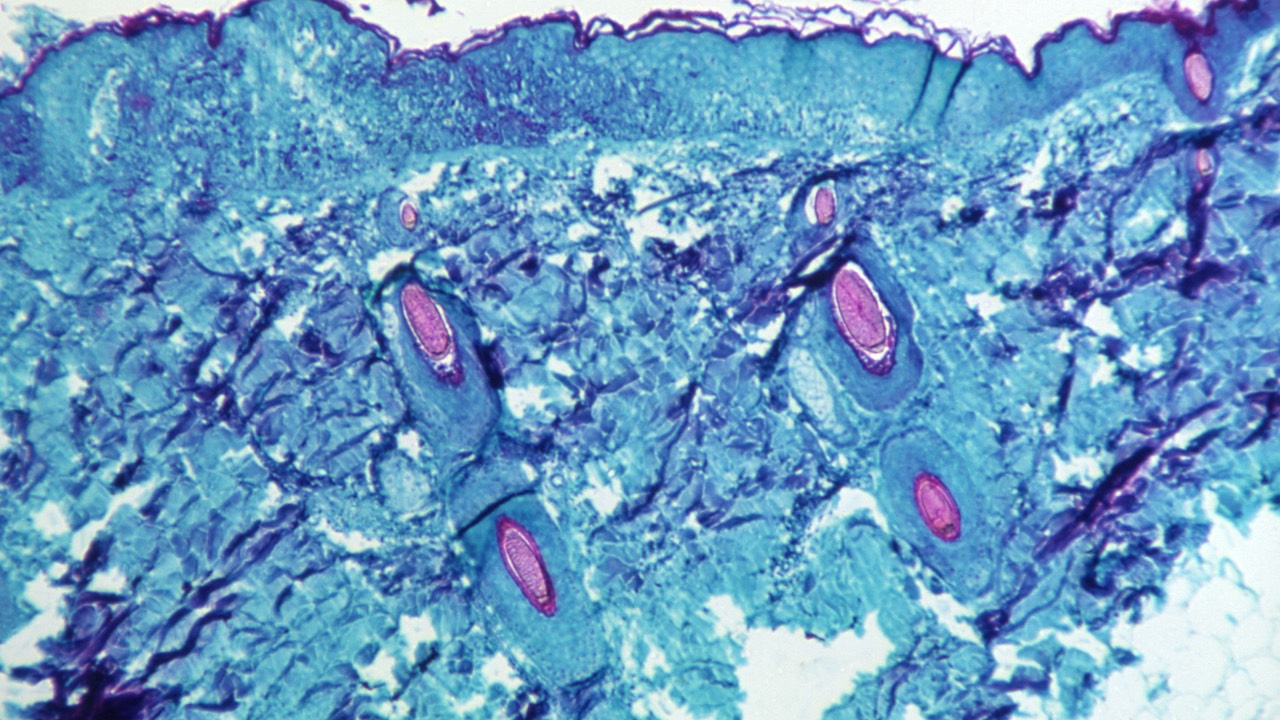

Monkeypox has not previously been reported as a sexually transmitted infection but it can be passed on by direct contact during intercourse. /CDC/Reuters